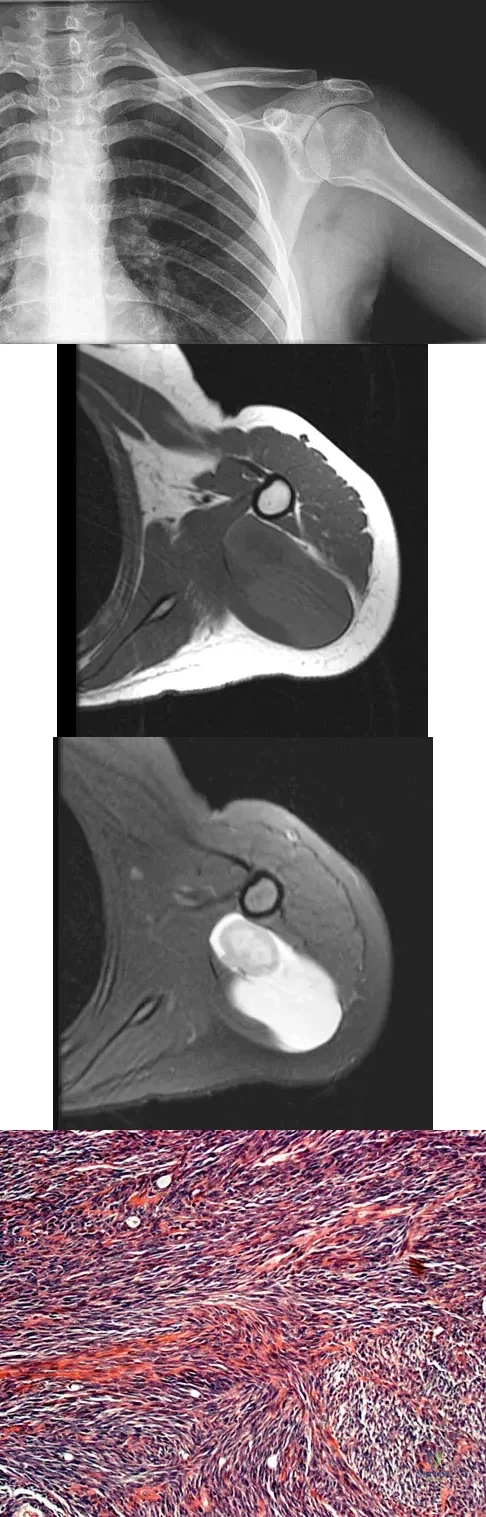

A 16-year-old girl has had painless swelling in her posterior left arm for the past 4 months. A radiograph, MRI scans, and an incisional biopsy specimen are shown in Figures 43a through 43d. What is the cytogenetic translocation most commonly associated with this tumor?

Explanation

This is a case of synovial sarcoma. The radiograph shows some soft-tissue swelling in the upper arm. The MRI scans show a lesion that has increased signal on T2-weighted images and low signal on T1-weighted images. There is a suggestion of a large cystic component to this lesion. The pathology shows a biphasic population of cells, a spindle cell component, and an epithelioid component. Up to 20% of synovial cell sarcomas have areas of cyst formation. The most common cytogenetic translocation with synovial cell sarcoma is X; 18. The 11; 22 translocation is most commonly associated with Ewing's sarcomas; the 12; 22 translocation is most commonly associated with clear cell sarcomas; the 2; 13 translocation is most commonly associated with alveolar rhabdomyosarcomas, and the 12; 16 translocation is most commonly associated with myxoid liposarcomas. Kawai A, Woodruff J, Healey JH, et al: SYT-SSX gene fusion as a determinant of morphology and prognosis in synovial sarcoma. New Engl J Med 1998;338:153-160.

References:

- Sandberg AA: Cytogenetics and molecular genetics of bone and soft tissue tumors. Am J Med Genet 2002;115:189-193.